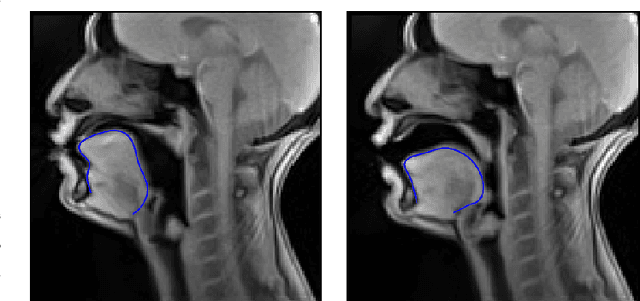

Abstract:Tongue contour extraction from real-time magnetic resonance images is a nontrivial task due to the presence of artifacts manifesting in form of blurring or ghostly contours. In this work, we present results of automatic tongue delineation achieved by means of U-Net auto-encoder convolutional neural network. We present both intra- and inter-subject validation. We used real-time magnetic resonance images and manually annotated 1-pixel wide contours as inputs. Predicted probability maps were post-processed in order to obtain 1-pixel wide tongue contours. The results are very good and slightly outperform published results on automatic tongue segmentation.

Abstract:Acoustic articulatory inversion is a major processing challenge, with a wide range of applications from speech synthesis to feedback systems for language learning and rehabilitation. In recent years, deep learning methods have been applied to the inversion of less than a dozen geometrical positions corresponding to sensors glued to easily accessible articulators. It is therefore impossible to know the shape of the whole tongue from root to tip. In this work, we use high-quality real-time MRI data to track the contour of the tongue. The data used to drive the inversion are therefore the unstructured speech signal and the tongue contours. Several architectures relying on a Bi-MSTM including or not an autoencoder to reduce the dimensionality of the latent space, using or not the phonetic segmentation have been explored. The results show that the tongue contour can be recovered with a median accuracy of 2.21 mm (or 1.37 pixel) taking a context of 1 MFCC frame (static, delta and double-delta cepstral features).